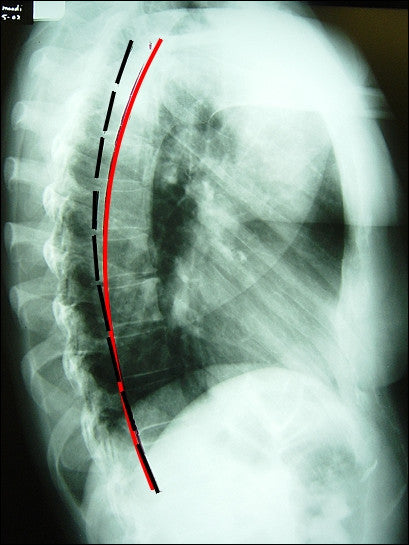

Ideal Thoracic Curve Template for Lateral Thoracic X-rays. Published in Spine 2003 This is the best ROF tool around! Simply distinguish your patients thoracic kyphosis curve from the normal range with this all new thoracic template. "Percentage Loss" sheet for calculating your patient's posterior tangent ARA measurement to a % loss from normal.